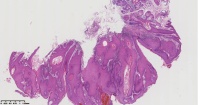

角化棘皮瘤?

性别

男

年龄

45岁

临床诊断

一般病史

面部包块

标本名称

图4

倾向脂溢性角化病。